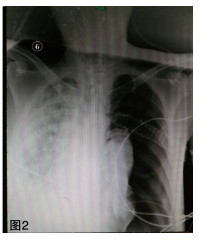

图 2 2016年11月21日床旁胸片提示左侧大量胸腔积气,右肺弥漫性渗出病变。 |

补液消酮、胰岛素控制血糖等对症支持治疗。11月3日患者酮症逐渐好转,但酸中毒进行性加重,最重时血气分析:PH 6.822,PCO2 21.4 mmHg,BE -27.7 mmol/L。最高体温39℃,并伴有患者神志改变,烦躁。左侧腹股沟伤口分泌物首次培养回报革兰阴性(G-)杆菌。予行左侧腹股沟伤口脓肿切开引流、气管插管、有创呼吸机辅助通气及床旁血液净化等ICU多脏器功能支持治疗。11月6日,患者血培养及伤口分泌物再次培养回报:类鼻疽伯克霍尔德氏菌(Burkolderia pseud-omallei, BP)。为求进一步明确,请实验室对患者腹股沟分泌物、血培养分离得到的2株细菌进一步鉴定,确认为同一菌种即类鼻疽伯克霍尔德菌。药敏试验仅对头孢他啶及亚胺培南敏感。两次查血G试验均明显升高,结合患者既往有糖尿病病史,不排外存在侵袭性全身真菌感染可能,治疗方案上调整抗生素为亚胺培南+氟康唑。2周后,患者体温逐渐降至正常,左侧腹股沟伤口愈合良好,血气、感染指标及肺部感染情况较前明显好转(如图 3)。给予降阶梯治疗,调整抗生素为头孢他啶1.5g q6h。21日患者突发胸闷、气促,伴大汗。急诊床旁彩超可见左侧胸膜滑动征消失及沙滩征(如图 4),胸片提示左侧大量气胸(压缩约90%)(如图 2)。11月27日再次出现胸闷气促,胸片提示右侧大量气胸(压缩约90%),治疗上予胸腔闭式引流术、肺复张、机械通气、足疗程抗感染、器官功能维持等。复查胸部CT变化(如图 5)。12月12日患者症状好转,成功撤机,拔除气管导管、转出急诊ICU至急诊观察病区。转出诊断:1.左侧腹股沟皮下脓肿;2.脓毒性休克;3.重症肺炎;4.糖尿病酮症酸中毒;5.多器官功能障碍综合征MODS(ARDS、AKI、DIC);6.双侧液气胸。患者与12月24日好转出院。